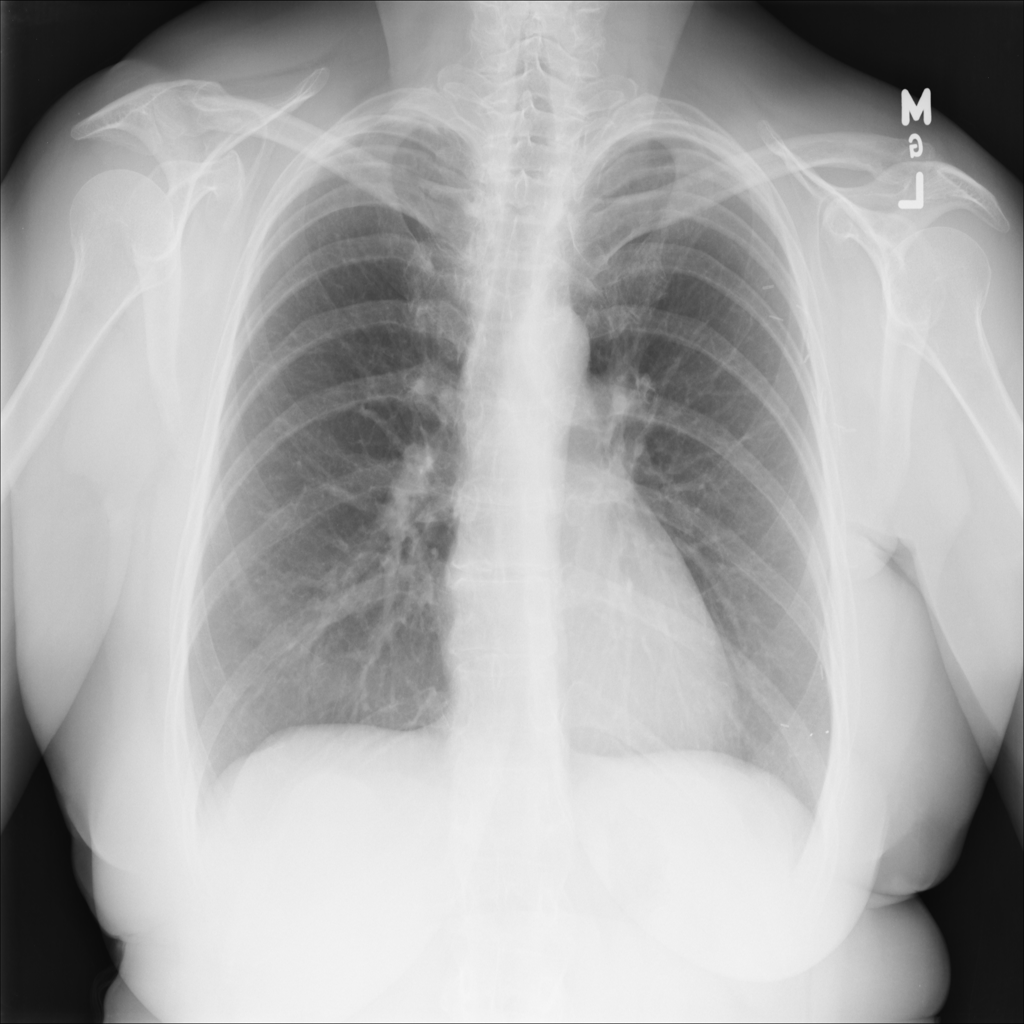

PAT-894B · IMG-000Emphysema

PAT-894B · IMG-000

PA